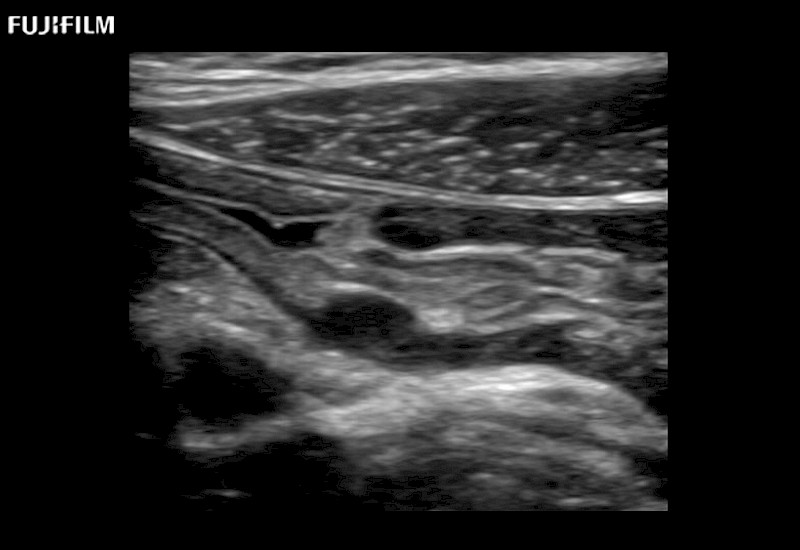

Learn moreFujifilm Healthcare continues to listen to the experts, our neurosurgeons, by developing an ultrasound system specifically designed for the Operating Room.

Guidance is the fundamental purpose for all of our surgical ultrasound technology. Fujifilm Healthcare is committed to designing tools that help neurosurgeons navigate inside the human body and provide the necessary information to immediately make critical surgical decisions.

With the ARIETTA Precision the next level of surgical ultrasound is here.